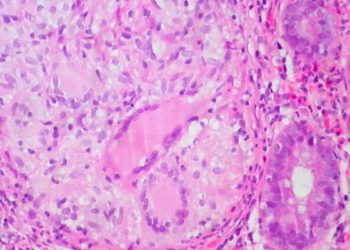

Vedolizumab as Induction and Maintenance Therapy for Ulcerative Colitis

Vedolizumab is a humanized monoclonal antibody targeting α4β7 integrin, which modulates gut lymphocyte trafficking and has shown efficacy for symptomatic relief in ulcerative colitis and Crohn’s disease in smaller phase II trials. Although similar in target to natalizumab (Tysabri), which antagonizes α4β1 and α4β7 integrin interactions to modulate CNS lymphocyte trafficking and has been used to treat MS, vedolizumab is reputed to have more gut specificity and avoid the limiting side effects of PML by JC polymoavirus reactivation. In these two phase 3 randomized, double blinded, placebo control trials, patients with active ulcerative colitis and Crohn’s disease were randomized to vedolizumab or placebo induction and maintenance therapy. In the ulcerative colitis induction trials, there was a statistically significant difference in clinical response (47.1% vs. 25.5%, p < 0.001) and a greater proportion of patients receiving vedolizumab had clinical remission (16.9% vs. 5.4%, p = 0.001). Similarly, for Crohn’s diease patients, there was a greater proportion of clinical remission at 6 weeks (14.5% vs. 6.8%, p = 0.02). For the ulcerative colitis maintenance trials, at one year there was a greater proportion of clinical remission in patients recieiving vedolizumab every 8 weeks and 4 weeks compared to placebo (41.8% vs. 44.8% vs. 15.9%, p < 0.001 for both comparisons). Results were similar for Crohn’s disease patients (39.0% for q8weeks, 36.4% for q4weeks, 21.6% for placebo, p < 0.001 and p = 0.004 respectively). No cases of PML were found in either study, however there were more serioud adverse events for Crohn’s disease patients receiving vedolizumab. Vedolimuzab potentially be an efficacious addition to the compendium of pharmacologic treatments for ulcerative colitis and Crohn’s disease.